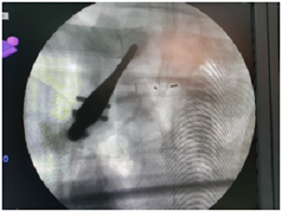

Burst fracture fixation and cementation

L3 fracture fixation